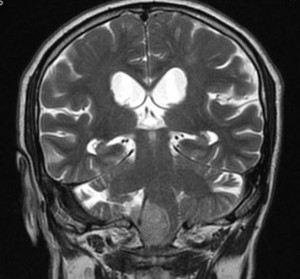

Ante una sospecha diagnóstica de algo patológico en lo que la imagen del TC no ha conseguido resolver nuestras dudas, realizamos una RM, en la que en T1 podremos ver mejor la estructura anatómica y en T2 podremos detectar la presencia de lesiones de diversa índole, sobre todo debido al edema del que se suelen acompañar.